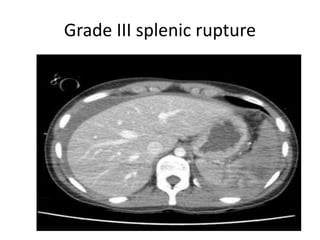

CT grading of splenic rupture.

• In it splenic lacerations appears as linear low

attenuation defects that contrast well with

high attenuation vascular spleen.

• Intra splenic hematomas appear as more

diffuse hypo-attenuating region with irregular

margins with splenic swelling.

Grade III splenic rupture